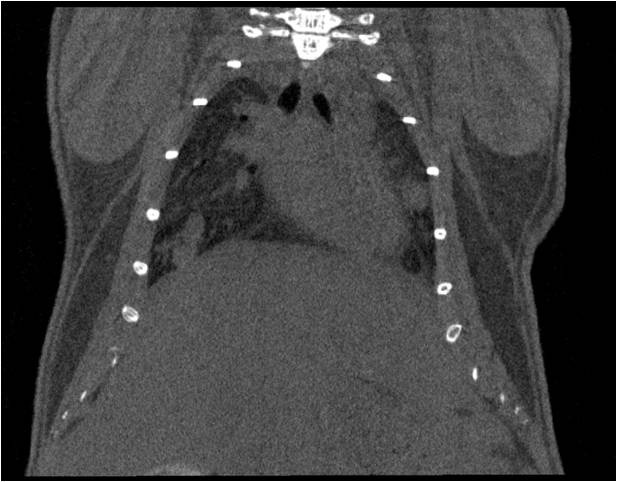

肺轉(zhuǎn)移

小鼠模式,22.5μm像素

正常

8天 14天

無造影劑注入 造影劑注入